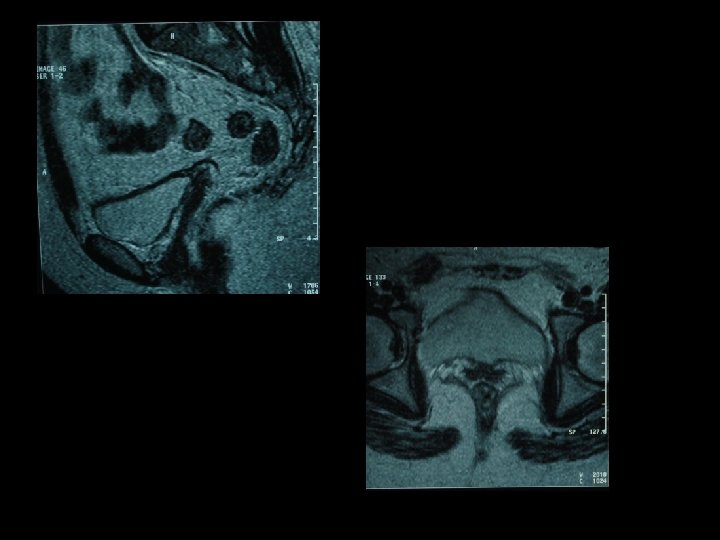

*l’échographie pelvienne a montrée : un utérus hypoplasique dépourvue de la ligne de vacuité mais avec des ovaires normaux. *L’IRM pelvienne a mis en évidence : des structures allongées hypo intenses en coupes axiales et coronales pondérées en T 2 correspondant à 2 cornes utérine rudimentaires.

*Aucune structure myométriale n’était visible en séquence pondérée en T 2 à l’emplacement habituel de l’utérus . *Elle a montrée aussi un reliquat vaginal et des trompes normaux avec des ovaires normaux haut situés. *Un complément d’échographie abdominale à la recherche de malformations associés a été réalisée : sans anomalies. Elle a été explorée par une cœlioscopie.

• Ovaires normaux + reliquats fibreux uterins

• Reliquats fibreux uterins

*L’IRM a un rôle important en cas de suspicion de syndrome de Rokitansky. *Elle permet de visualiser l’état de développement de l’utérus, cependant la détection des cornes utérines rudimentaires est parfois difficile. *Elles sont visibles comme des structures hypo intenses allongées, ovalaires « en forme d’épi de maïs » sur les séquences axiales et coronales pondérées en T 2.